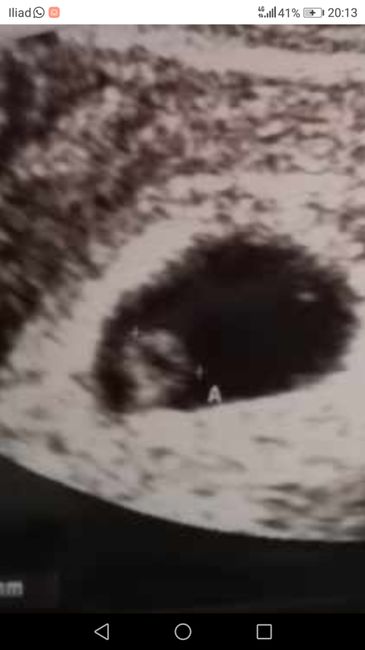

Metodo Ramzi! Chi ci sa azzeccare?

Buongiorno!! Chi è brava a spiegarmi il metodo Ramzi e sa azzeccarci? 😊